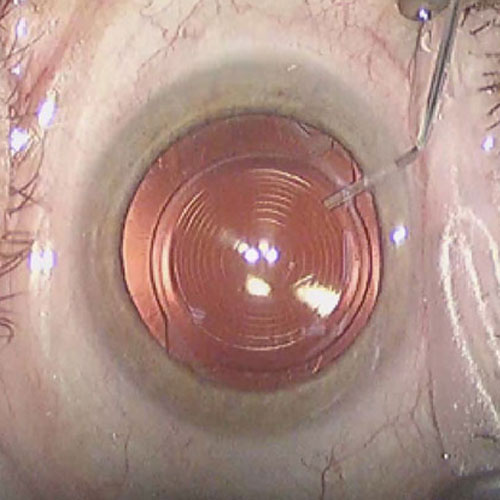

Dr. Abdul Rasheed, one of the leading Ophthalmologist and Cataract & Refractive surgeon in the city of Hyderabad provides extensive and comprehensive care for all your eye sight issues. Vision disturbance are one of the few issues which have the capacity to completely disturb our daily life and activities. Correcting them in the right way to avoid further complications or risk is the motto of Dr. Abdul Rasheed. With age comes cataract, Dr.Rasheed is an expert in complicated cataracts such as small pupil, zonular dialysis, mature / Brunescent cataracts, corneal scars, shallow Ac, etc., as well as complicated refractive surgery cases like RK scars, corneal scars, etc. While coming to refractive surgeries, Dr. Abdul Rasheed strongly believes and says "Any patient irrespective of complexity, who can be refracted to 6/6 can be treated to read the same without glasses." He has treated many patients of keratoconus who had extreme distortion of vision. After INTACS implantation followed by ICL, patients were able to regain normal vision.